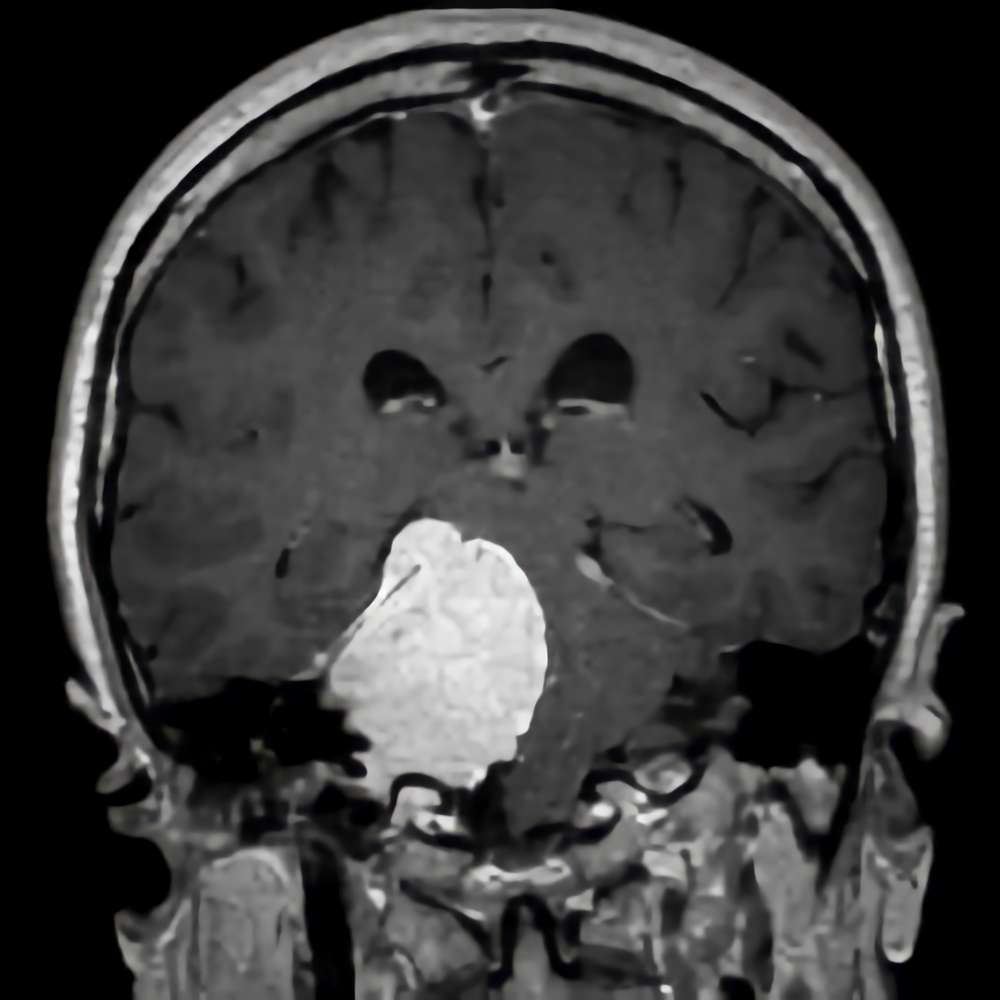

281

'22年4月

70代

左小脳橋角部髄膜腫

頭蓋内腫瘍摘出術

No.’22_38 手術前1

No.’22_38 手術前2